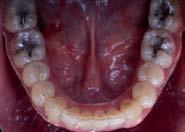

Paciente de 14 años y 8 meses, moti vo de consulta: “mi mordida no me gusta” el patrón esquelético es cla se II, hiperdivergente, clase II molar derecha y clase I molar izquierda, los caninos superiores en infraoclusión overbite disminuido, apiñamiento severo superior, moderado inferior, con los dientes 12 y 22 palatinizados, el 13 ectópico, con mordida abierta anterior, y las líneas medias desvia das.

Estudios de inicio fotografías intrao rales en la de frente se ven la línea media dental superior esta desviada

hacia la derecha y la línea media dental inferior a la izquierda, con mordida abierta anterior, el canino superior derecho se encuentra fuera del arco ( Figura 3 ), en la oclusal superior los inci sivos laterales palatini zados y paladar ojival profundo, en la lateral derecha una relación molar clase II y relación canina no determinable (Figura 4), en la izquier da una relación molar clase I y relación canina no deter minada.

172. Diciembre 2022 Corrección de mordida abierta anterior por deglución atípica Figura 3. Intraoral inicial de frente, la oclusal superior forma de arco triangular.